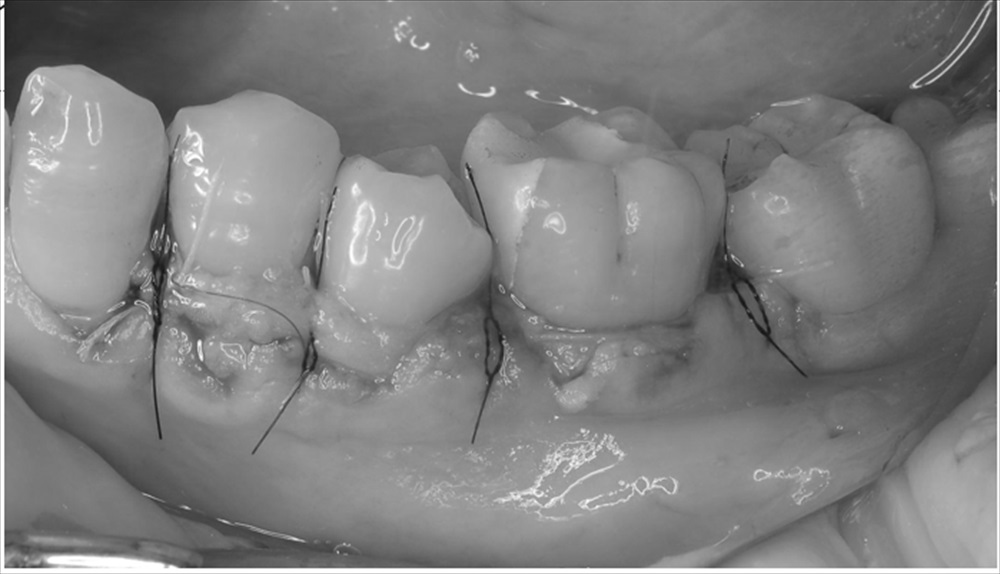

結合組織移植を行い

手術後